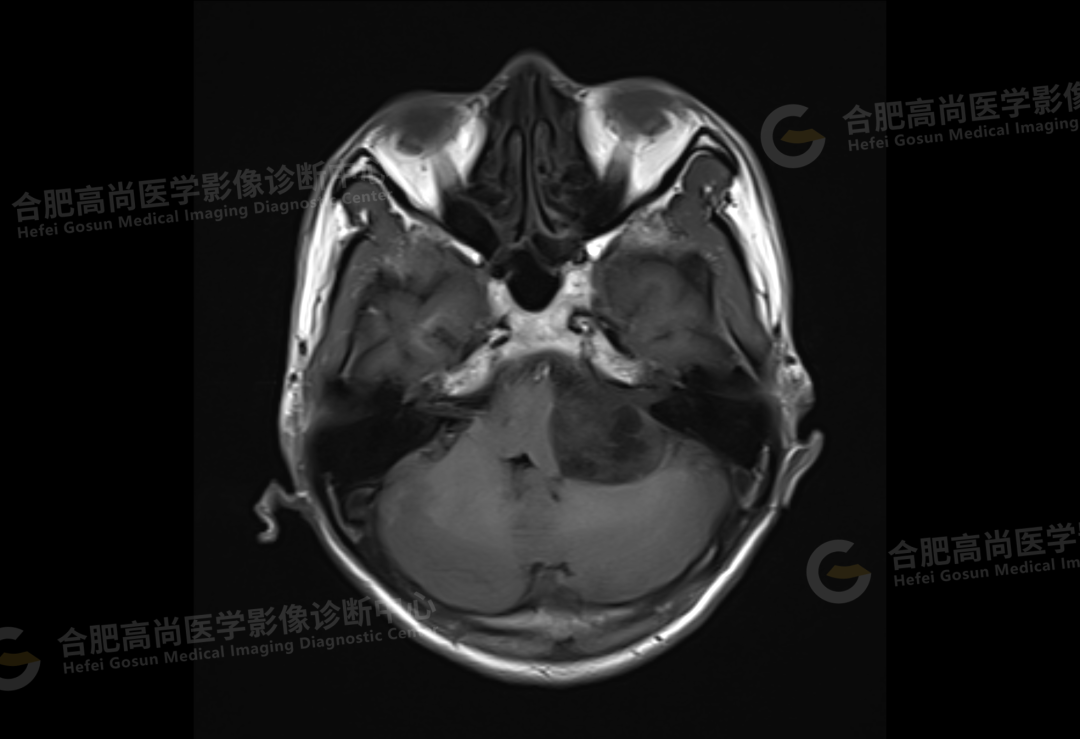

2、颅脑 MRI

颅脑 MRI 平扫+增强显示:左侧桥小脑角区可见类圆形囊实性异常信号,呈长 T1 长 T2 信号,flair 序列呈混杂高信号,内可见坏死囊变,大小约 3.0*3.5 cm,边界清晰,增强后病灶实性成分明显强化,囊变区未见明显强化,左侧内听道扩大,听神经增粗伴明显强化,病灶邻近小脑及桥脑受压推移变形,四脑室变形变窄,对侧桥小脑角区未见异常。

结论:左侧桥小脑角区占位,考虑听神经瘤。